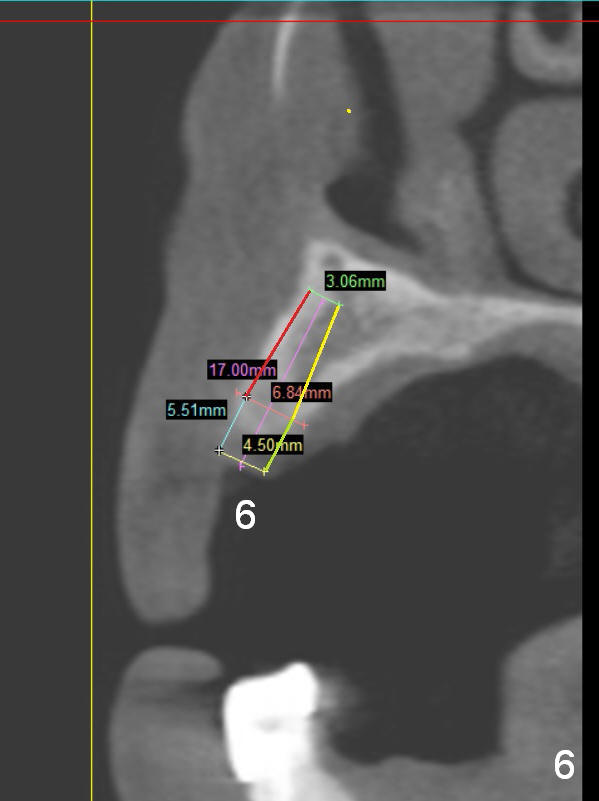

A 68-year-old lady has several missing teeth (Fig.1,2). She has agreed to have an implant at the site of #3 (Fig.3) to stabilize an upper removable partial denture (RPD). The latter will be more stable if an extra implant is placed at #6 (Fig.1,2,6). There is enough bone to place implants at #4,5 (Fig.4,5). Bone density at these sites is low. Osteotomy should be underprep with bone condensation. Edentulous space is high so long abutments are required (9 mm instead of 3 or 5 mm (regularly used)). Angled abutments should be prepared.